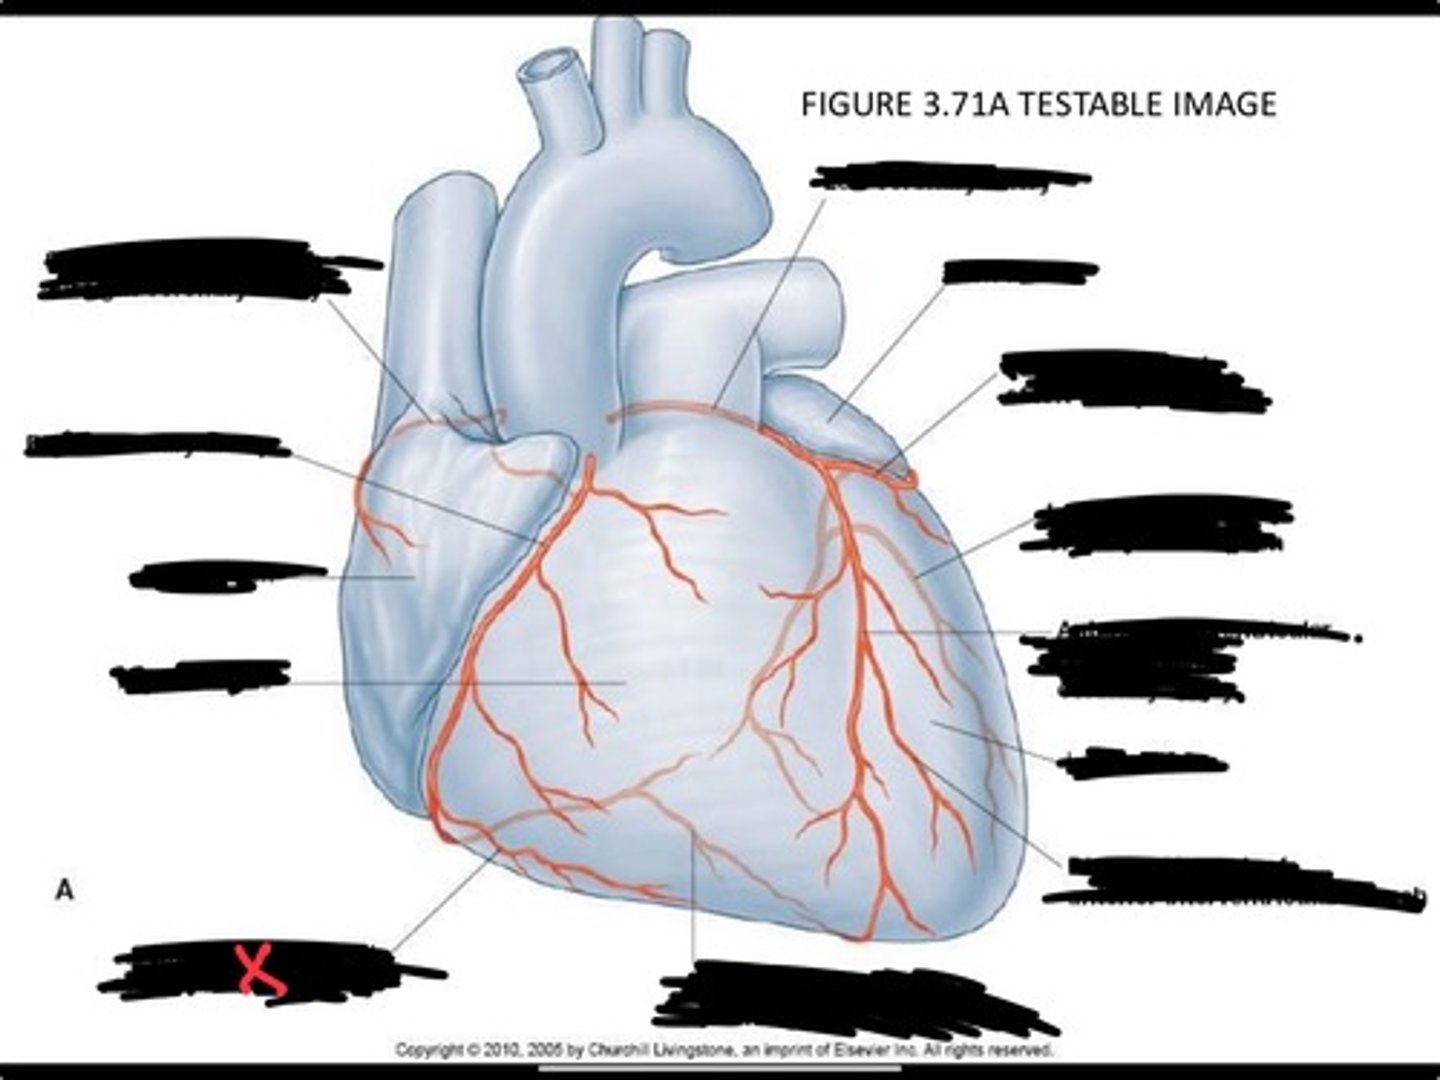

Pulmonary veins

Posterior interventricular branch of right coronary artery

Right arginal branch of coronary artery

Right ventricle

Right atrium

Right coronary artery

Sinu-atrial nodal branch of right coronary artery

Left coronary artery

Left auricle

Circumflex branch of coronary artery